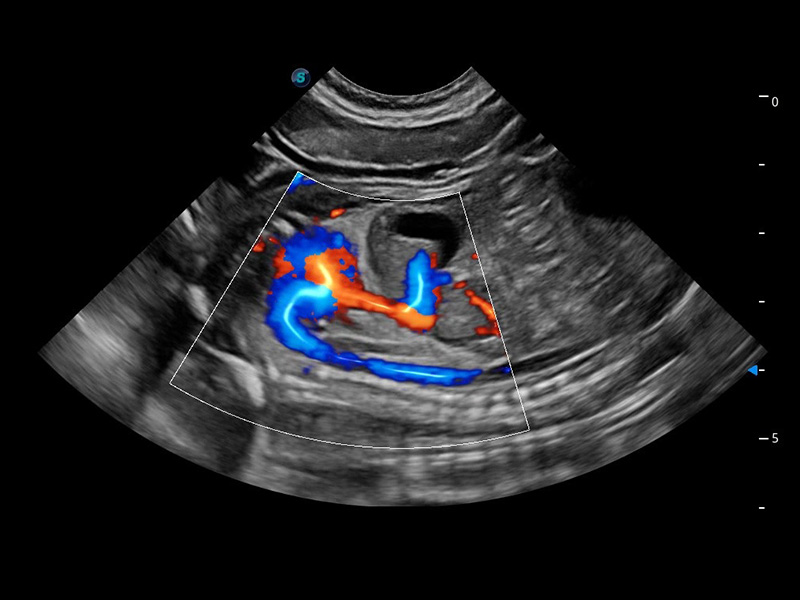

ProPet 60 作为一款高端台式动物超声设备,为动物医生的日常诊断提供了一系列贴合动物临床需求、解决临床实际问题的高级成像功能。凭借全系列高清探头,满足医生对腹部、心脏、生殖、浅表、肌骨等成像的所有需求,切实帮助您提升检查效率,提高诊断信心。

动物是人类最亲密的朋友和最值得信赖的伙伴。美狮贵宾会官网也一直致力于探索动物专用的超声影像解决方案。 全新推出的ProPet系列,是美狮贵宾会官网在动物超声影像智能化、专业化、精准化的一次跨越式革新。动物不能用言语来表述自己的不适,通过超声影像,ProPet系列搭建了动物医生与不同物种沟通的“桥梁”,为动物医生注入了“治愈之力”。